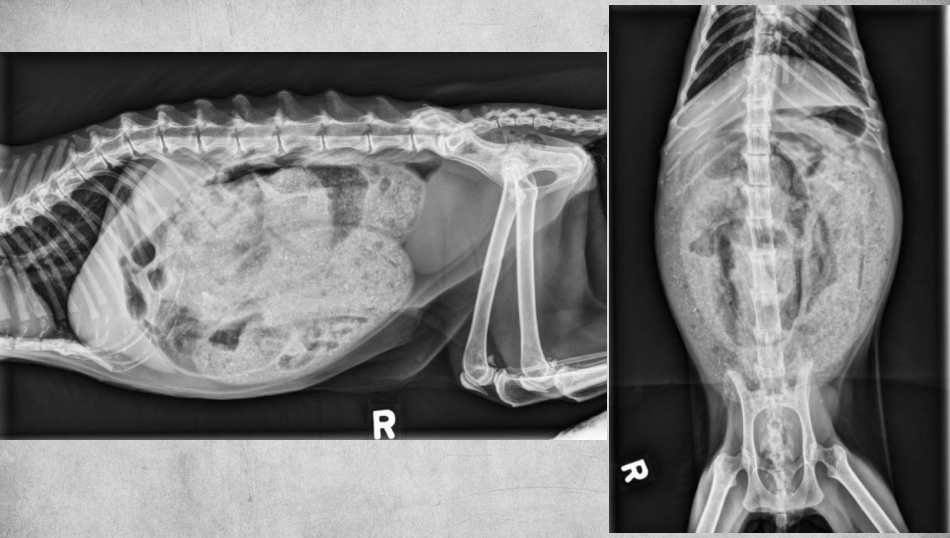

●9 yo mixed breed female dog

(sterilized)

●Increased ALP

● Impressive amount of subcutaneous and intra-abdominal fat.

● Enlarged liver – changed gastric axis pushed caudally, rounded edges, extending past the costal arch.

● At least two round soft tissue opacity structures superimposed on ventral liver (lateral view).

● Round soft tissue structure cranial to right kidney.

● Mass in adrenal gland or pancreas

● Hepatic nodules (benign vs metastatic disease)

SI gas is normal because bowels empty.